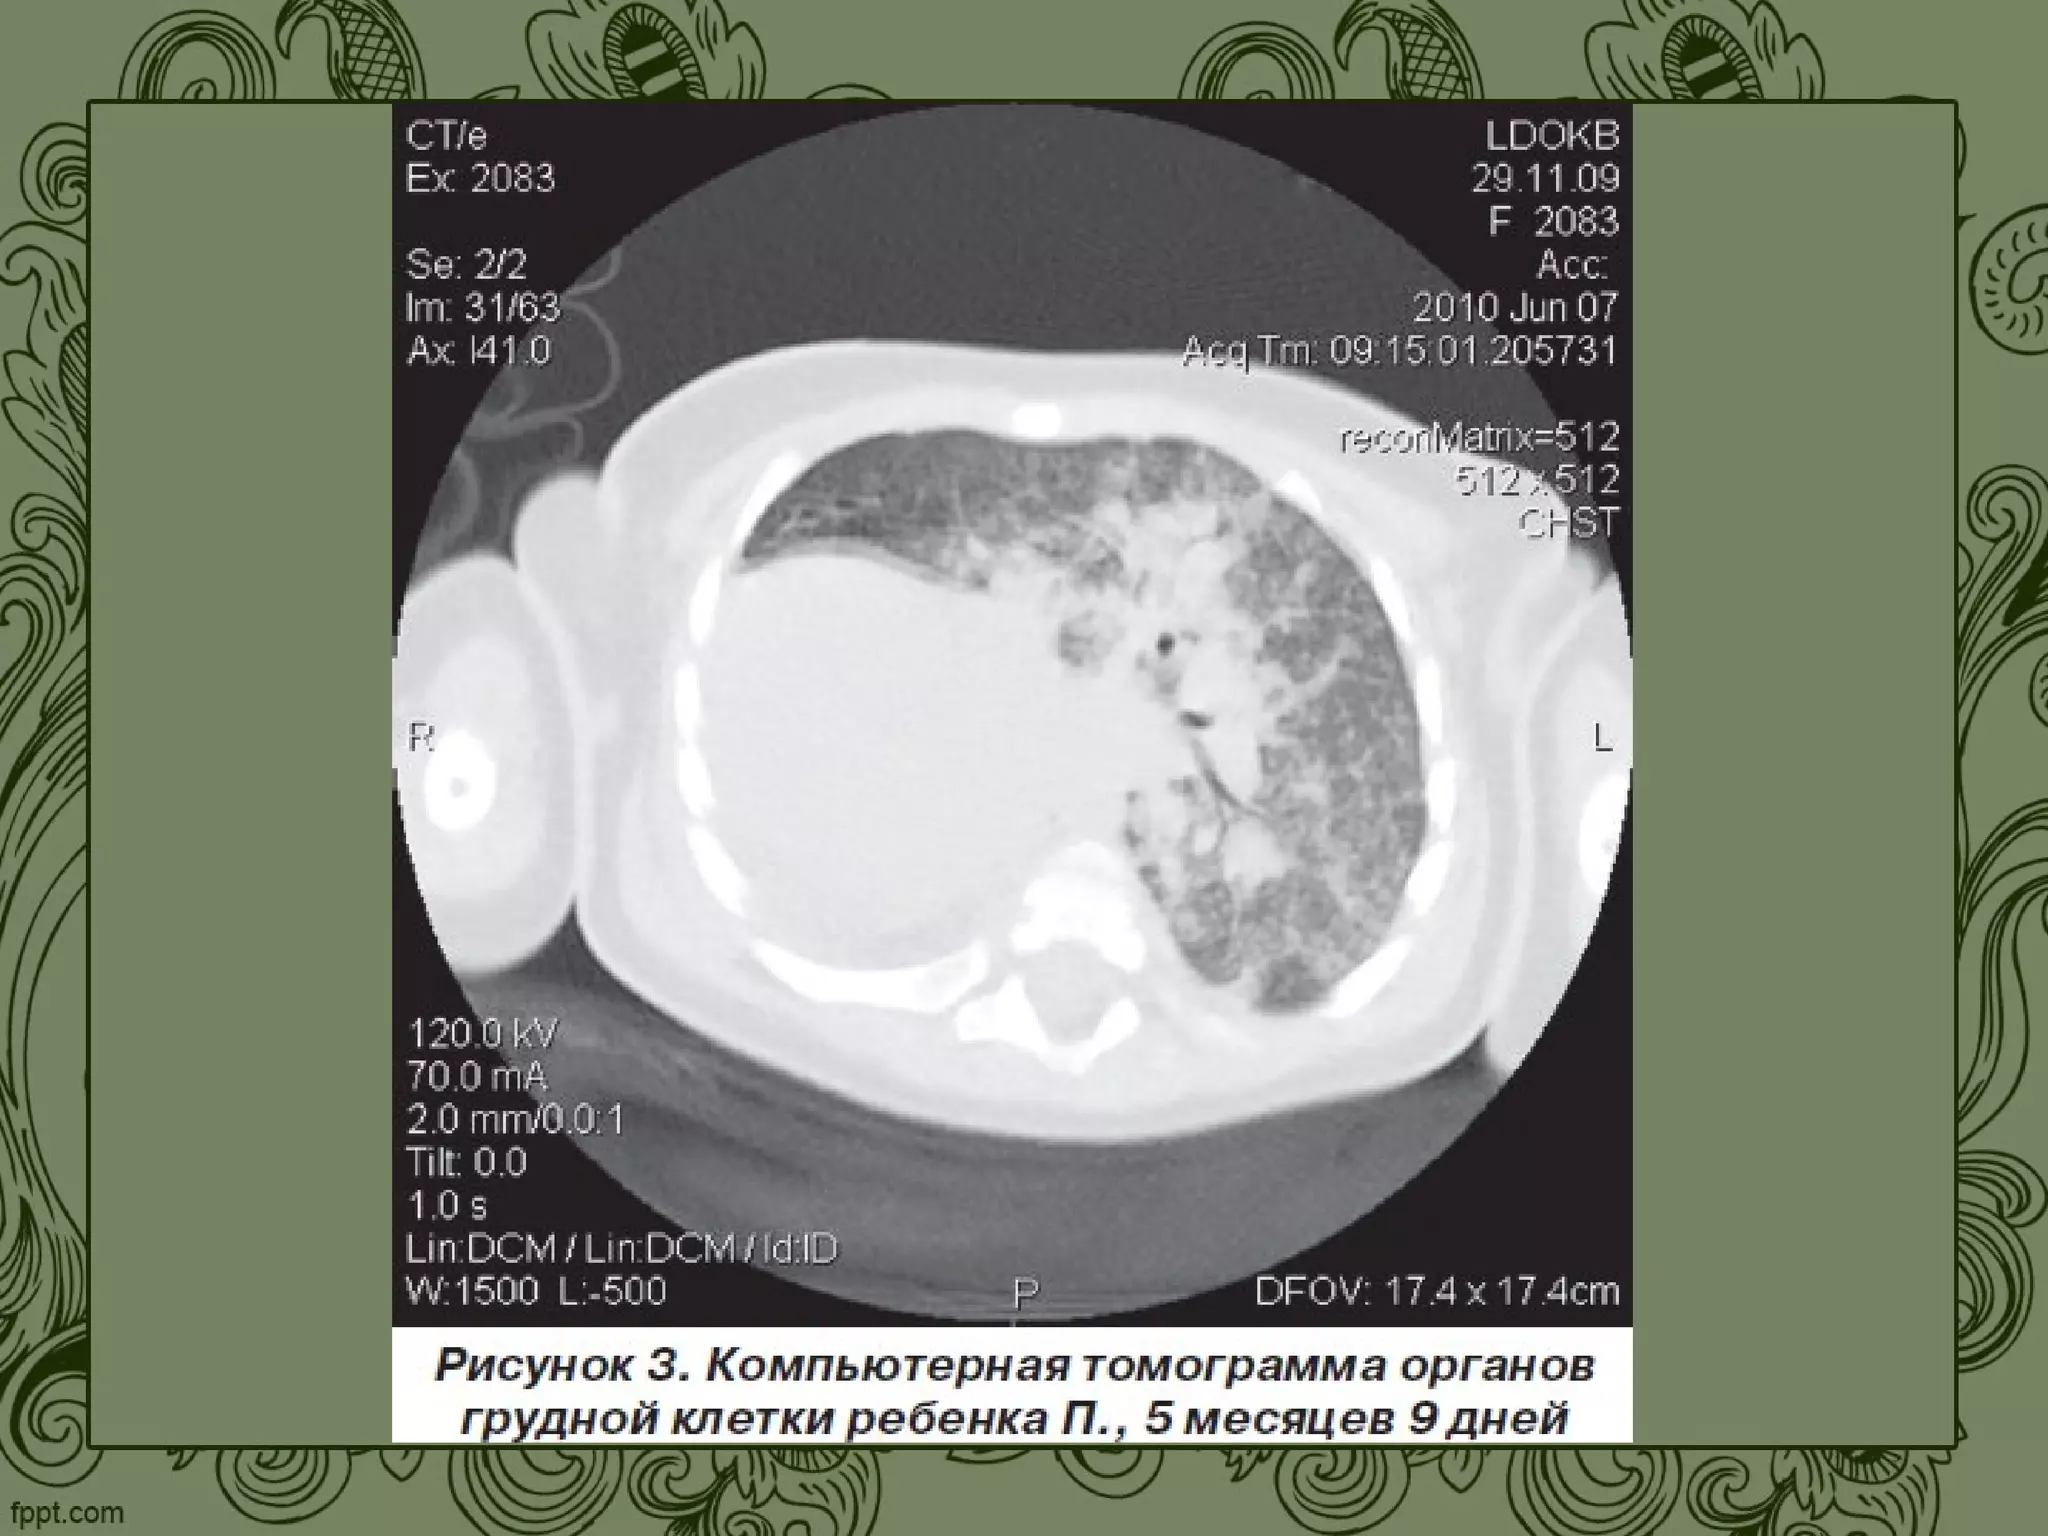

Аплазія та гіпоплазія легень. Дефіцит альфа-1-антитрипсину.